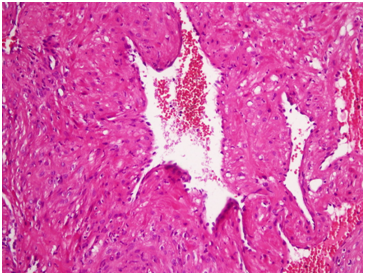

The mass measured 7mm *7mm *5mm. Microscopic examination showed variable sized blood vessels with thickening of the wall by thick muscular layer merging within smooth muscle bundles. Focal adipose metaplasia identified. No hemorrhage, necrosis, mitotic activity, vasculitis, or fibromuscular dysplasia observed, Figure 2.

Figure 2 Hematoxylin and eosin stain histopathological microscopic appearance of the lesion.